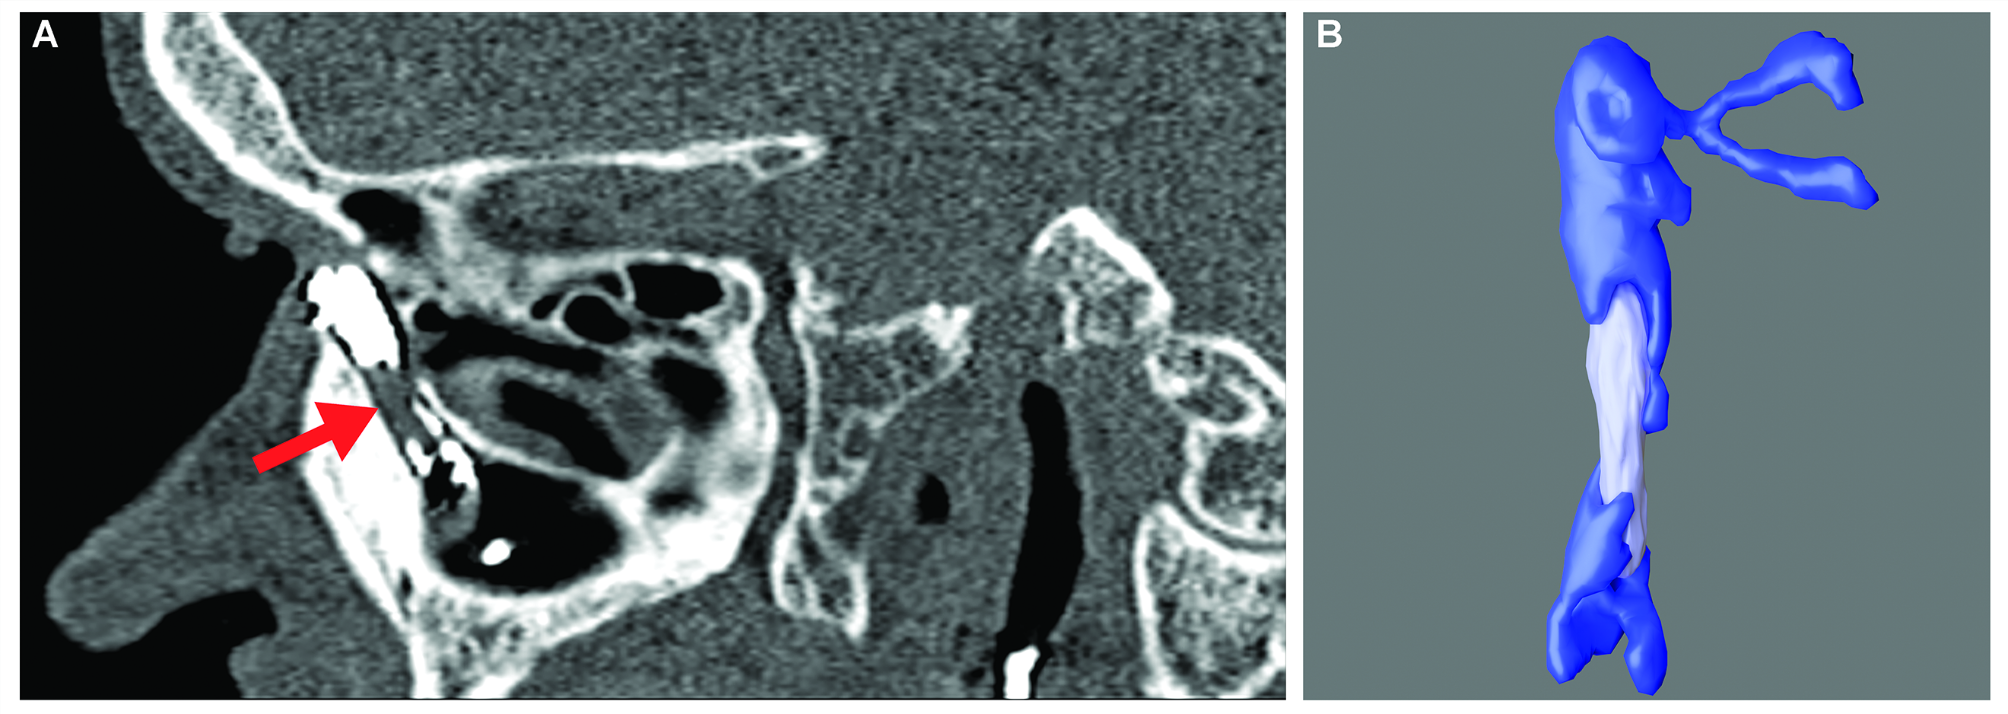

Fig. 2

CT-DCG sagittal section of a patient with a large nasolacrimal duct dacryolith reflected as a filling defect (red arrow, A). 3D-CTDCG reconstructed model demonstrating the accurate reconstruction of the dacryolith (B).